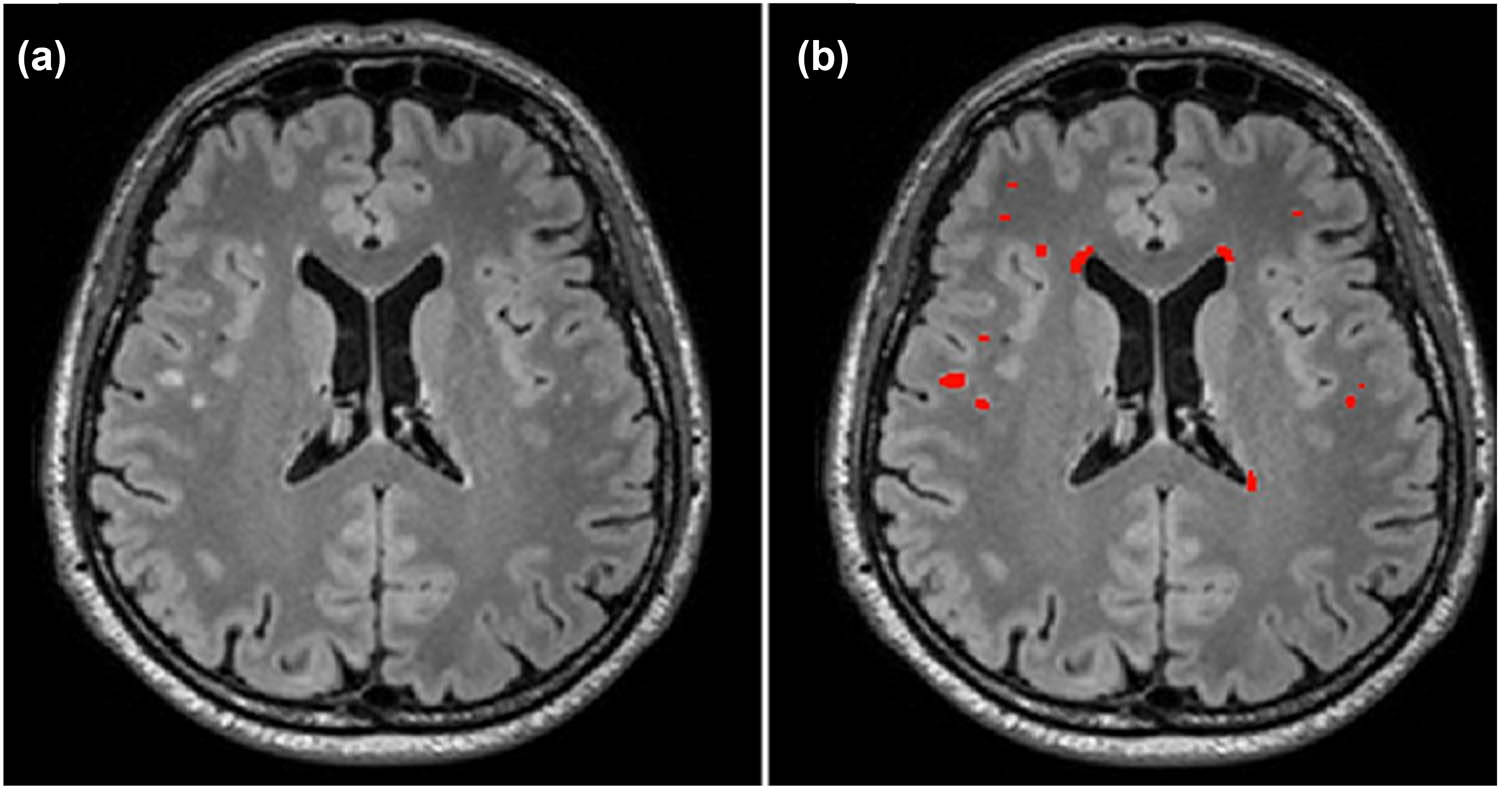

WMHs are high-intensity areas on MRI scans associated with an increased risk of stroke, cognitive decline, and depression. Identifying the risk factors for WMHs is crucial. Beyond age and hypertension, WMH is significant in both prediabetes and diabetes [13] (Figure 5). T2DM patients often exhibit an abnormal increase in WMHs, which correlates with a higher cardiovascular risk, larger WMH volumes (indicative of white matter dysfunction), slower processing speeds, and attention deficits [14].

![Figure 5

Illustration of manual segmentation for WMHs (total WMH volume: 1,835 mm3). (a) Axial T2-weighted FLAIR image from a study subject in his fifth decade. (b) Segmented WMH volume is highlighted in red. The segmentation was performed using ITK-SNAP version 3.6.0. WMH refers to white matter hyperintensity. Reproduced with permission from ref. [13]. Copyright 2021, BMJ Journals.](/document/doi/10.1515/med-2025-1253/asset/graphic/j_med-2025-1253_fig_005.jpg)

Illustration of manual segmentation for WMHs (total WMH volume: 1,835 mm3). (a) Axial T2-weighted FLAIR image from a study subject in his fifth decade. (b) Segmented WMH volume is highlighted in red. The segmentation was performed using ITK-SNAP version 3.6.0. WMH refers to white matter hyperintensity. Reproduced with permission from ref. [13]. Copyright 2021, BMJ Journals.